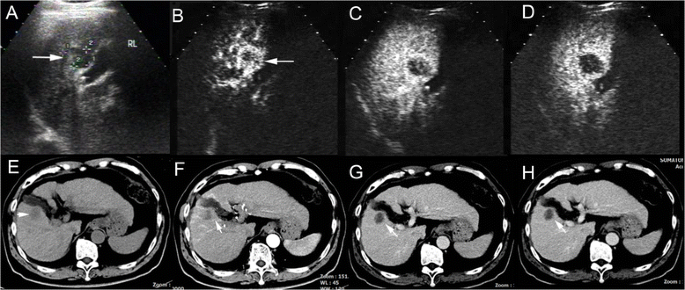

cHCC-CC in a patient with cirrhosis related to chronic hepatitis B infection. CA19-9 test was normal and AFP elevated (178.5 ng/ml) in discordance with presumptive imaging findings in the patient. Unenhanced ultrasound shows a hypoechoic nodule (a, arrow) of 2.7 cm in right lobe of the liver (RL). The nodule demonstrates peripheral rim-like enhancement in the arterial phase (b, 18 s after contrast agent injection, arrow) followed by quick (c, 37 s after injection) and marked washout (d, 82 s after injection) in the portal phase on CEUS, resembling the enhancement pattern of intrahepatic cholangiocarcinoma. Unenhanced CT scan reveals a hypodense nodule in right lobe of the liver (e, arrow). The nodule displays peripheral rim-like enhancement in the arterial phase (f, arrow) followed by stable and persistent peripheral rim-like enhancement in the portal (g) and the late phase (h, arrow), resembling the enhancement pattern of intrahepatic cholangiocarcinoma